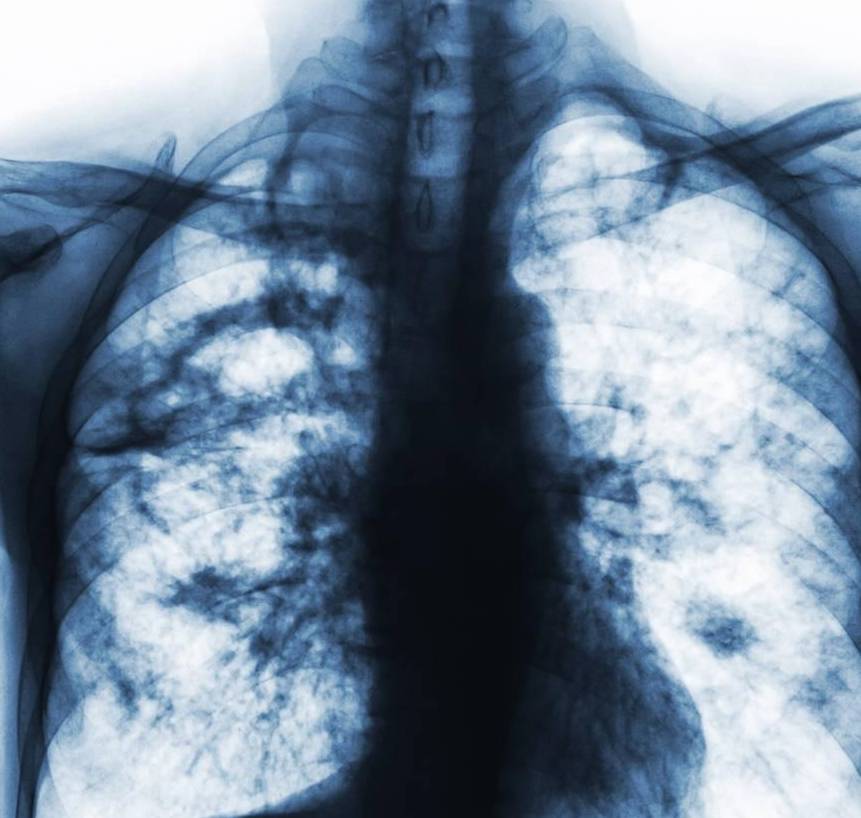

— 老年人肺炎不但要“治”,更要重视“防”!如何预防老年人肺炎? —